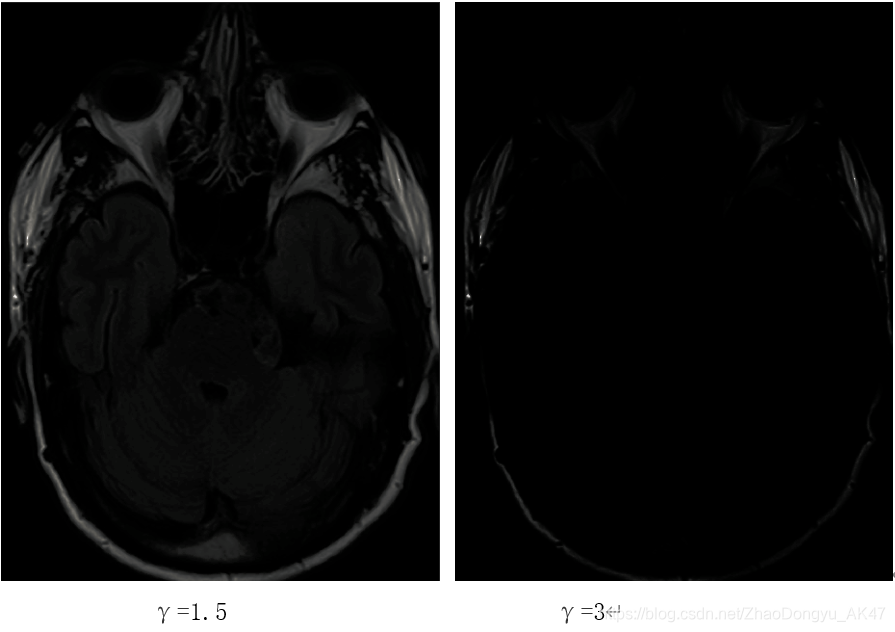

分析:

如幂次变换特点——当γ<1,此时扩展低灰度级,压缩高灰度级,使图像变亮;当γ>1,此时扩展高灰度级,压缩低灰度级,使图像变暗。

感觉在γ为0.4时相比于0.6的一些细节更清晰一些,当γ为0.2时图片有点过亮,一些细节反而不容易观察。

而当γ大于1时,原本就比较暗的图像变得更暗,基本上无法观察了。